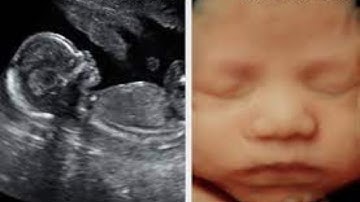

What is 4D ultrasound scan?